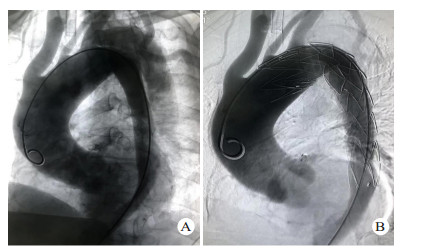

1.3 手术方法除1例主动脉夹层患者合并严重骨盆骨折及全身多处器官损伤,因失血性休克于入院后3 h死亡,其余13例患者均在全麻或局麻下行TEVAR。所有患者均在入院后48 h内完成TEVAR。TEVAR在数字减影血管造影(digital substraction antiography,DSA)室进行,转流手术及其他脏器手术在手术室进行。11例患者采用全身麻醉,2例采用局部麻醉。手术切口均腹股沟切口进行。患者取仰卧位,两侧腹股沟区充分消毒,铺无菌巾,经腹股沟切口暴露股动脉,Seldinger方法穿刺股动脉,置入5 F导管鞘,插入标记导管,将导管置于膈肌平面,注入造影剂,了解主动脉有无其他破口及腹腔重要血管分支供血情况,最后将导管尖端置于升主动脉,行正位及45°左前斜位行主动脉造影,明确主动脉破口位置及真假腔情况(图 2A),测量锚定区主动脉直径,选择合适大小的覆膜支架,进超硬导丝,取出导管及导管鞘,将支架系统输送至锚定区,定位准确后释放覆膜支架,再次造影明确夹层破口覆盖情况(图 2B),左侧锁骨下动脉供血情况,及有无内漏等。合并血胸患者行TEVAR后在介入室立即行胸腔闭式引流,并控制引流速度及引流量。伴有其他合并伤需手术的患者在进行TEVAR后转至手术室行合并伤手术; 同期脾切除、肠穿孔修补、剖胸探查止血各1例,TEVAR后2周后行骨折内固定术2例。术后所有患者均返回本重症监护室进行进一步治疗。

| 图 2 患者23岁,因高处坠落伤入院,入院后诊断TAD,破口大,急诊行TEVAR(A:术中主动脉造影显示破口位于降主动脉峡部,靠近左侧锁骨下动脉,真腔小,假腔大; B:术中再次主动脉造影,夹层破口封闭满意,无内漏) |